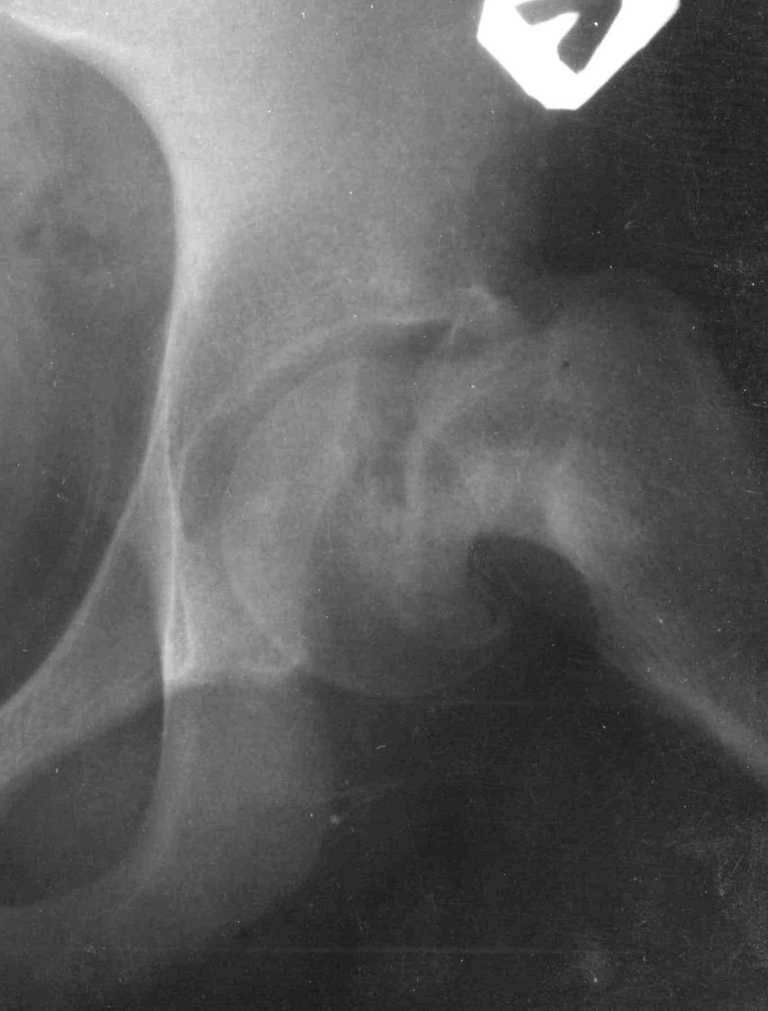

Ребёнок 14 лет. Весом под центнер. Имеющаяся рентгенологическая деформация деформация - на момент поступления. Госпитализирован ребёнок 14 лет. Мальчик, мягко говоря, крупный, гиперстенического типа сложения, ближе к десантнику. Весит 95 кг. Ожирение 2-й степени. Со слов больного - испытывает дискомфорт в области тазобедренного сустава в течение 3-х месяцев. На рентгенограммах - положение дел на момент поступления - конец мая. Укорочение конечности на 1,5 см. Ограничение внутренней ротации. Ходит, едва заметно прихрамывая на больную ногу. Эндокринологический статус находится в стадии обследования. Выполнена рентгенография в стандартных укладках, спиральная КТГ.Ясное дело, головка бедра <ушла> вниз и кзади. Пытающаяся <поймать> её шейка варизировалась и исполнила ретроверсию, создав изгиб во фронтальной плоскости. На рентгеноскопии - подвижность головки не определяется. Мальчик имеет далеко идущие планы на обустройство собственной жизни и образование. Крайне негативно относится к длительной иммобилизации и консервативному лечению. Загодя не согласен со снижением качества жизни в процессе лечения. Мнения коллег относительно дальнейшего лечения разделились. Успешность репозиции головки под наркозом - сомнительная в связи с имеющейся деформацией шейки бедра. Одни склоняются к тактике невмешательства - разгрузка больной конечности, ФЗТ , массаж, и т.д. Предлагают ждать завершения процесса <сползания> головки в условиях полной разгрузки, <тянуть> сустав до эндопротезирования как можно дольше. Другая группа коллег предлагает немедленную стабилизацию головки, что, кажется, правильно. Принимая во внимание анатомическое соотношение головки и шейки бедра, способ остеосинтеза так же вызвал массу споров, не приведших к единому и окончательному мнению. Пока дискуссия остановилась на стабилизации спицами Бека под контролем ЭОП, возможно с применением электродов для проведения электростимуляции слабыми импульсными токами. Техника проведения спиц, однозначно, будет сопряжена с техническими трудностями, обусловленными имеющейся деформацией шейки. Как бы Вы поступили, коллеги, в данной ситуации?Заранее спасибо. И прошу прощения за качество спимков. Буду отправлять их по очереди.

Здравствуйте Данил. По представленным рентгенограммамам и кт срезам Вы имеете дело хронической, стабильной формой ЮЭГБК. Шеечно- эпифизарная деформация выраженная, эпифиз отклонён кзади более чем на 70 градусов, практически до упора в межвертельную ямку, что характеризует её как тяжёлую степень. В выборе метода лечения мы придерживаемся следующей схемы: